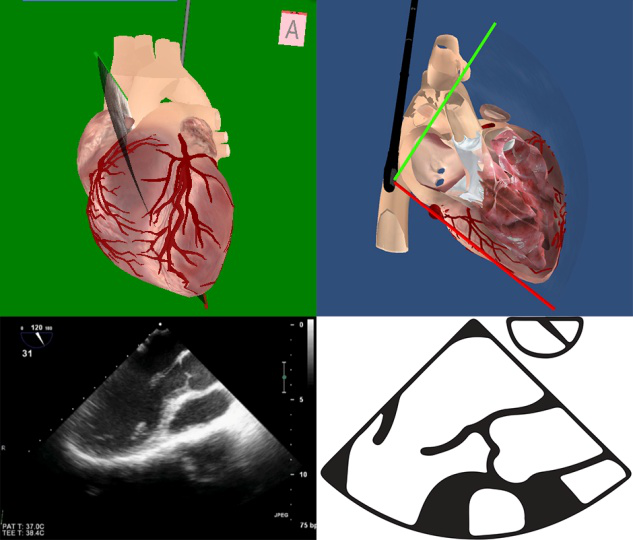

TEE切面与二尖瓣分区的对应关系可用于二尖瓣脱垂部位的判断,但要注意的是:一定要将2D或3D图像与二尖瓣模型对应起来,不理解切面和模型之间的空间关系,直接用文献上的分区对应实际的超声图像会导致定位不准和交流障碍(图11,12,13,14);另外,经胃底基底段短轴切面对诊断瓣叶裂和穿孔很有帮助,彩色多普勒可以提供有关反流束起源的信息(图14)。

图11四腔心切面显示二尖瓣后叶P2区脱垂

图13食管中段左室长轴切面显示二尖瓣后叶P2区腱索断裂并脱垂